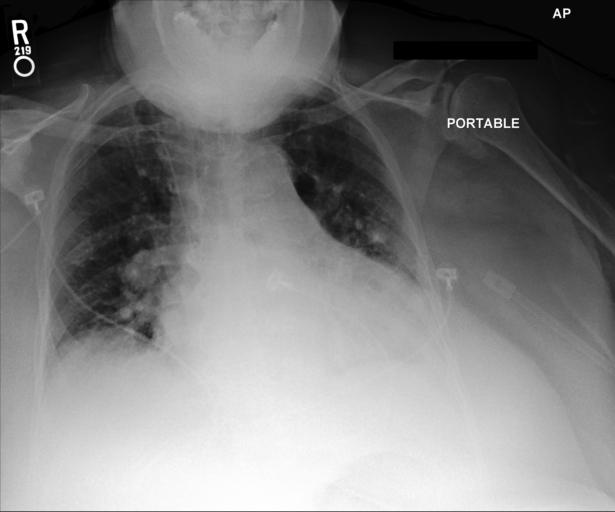

Refer to caption

Figure 1: Illustrative cases of medical hallucination include the following: (a) The model incorrectly answers a context-dependent medical question; the correct response should be “No.” (b) The model fabricates clinical knowledge, proposing “pleural effusion” and “asthma,” whereas the appropriate diagnoses are “lung cancer” or “pulmonary edema.” (c) The model hallucinates the nonexistent symptom “pleural effusions” and overlooks diffuse indistinctness of the pulmonary vasculature—a radiographic finding characteristic of “pulmonary edema”.